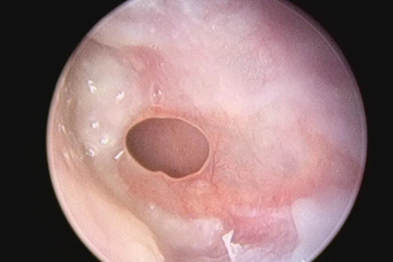

鼻子总不通?是两大「堵神」在作怪